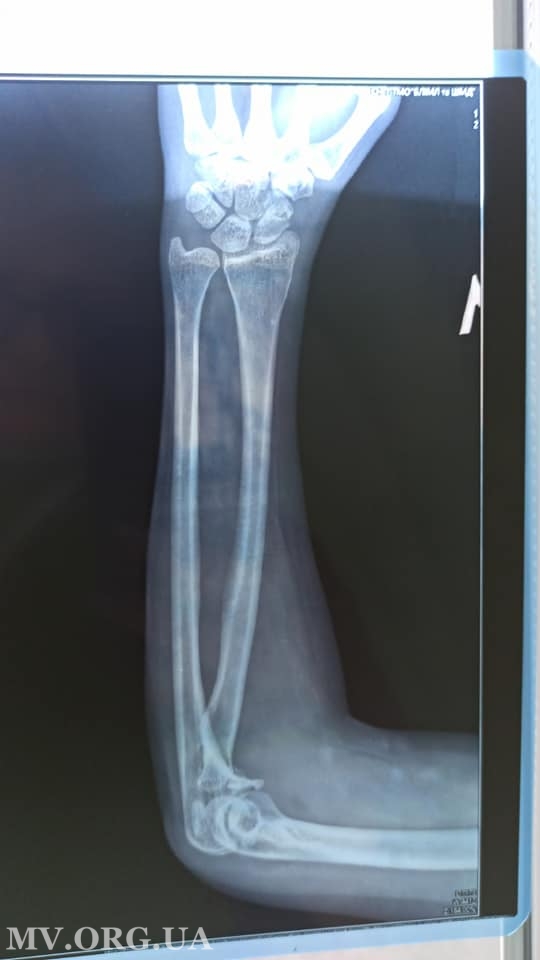

К посту-просьбе прилагается рентген снимок и заключение врача, в котором указано, что у велосипедистки "перелом венечного отростка левой локтевой кости со смещением и оскольчатый перелом головки левой лучевой кости".